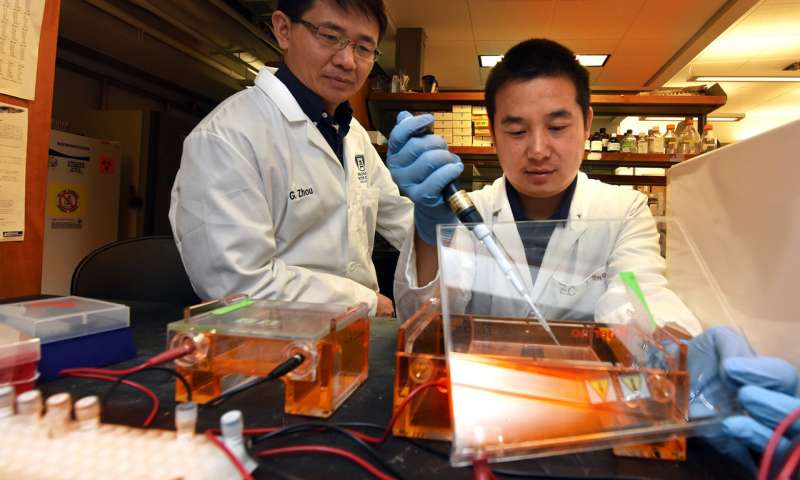

“La terapia delle cellule T adottiva sembra riprogrammare il metabolismo delle cellule tumorali, aumentando il loro livello di specie reattive dell’ossigeno o ROS e la loro distruzione”, dice il Dr. Gang Zhou, immunologo presso il Georgia Cancer Center e Dipartimento di Medicina presso il Medical College of Georgia all’Università di Augusta.

“La terapia sembra fornire un doppio-whammy mortale alle cellule cancerose”, dice Zhou, autore corrispondente dello studio pubblicato sulla rivista Cell Metabolism.

“Abbiamo iniziato ponendoci domande su come l’immunoterapia può modificare il metabolismo delle cellule tumorali. I nostri studi dimostrano che il fattore di necrosi tumorale alfa può agire direttamente sulle cellule tumorali e indurre ROS al loro interno”, afferma Zhou.

“Comparativamente poco focus c’è stato su ciò che le cellule T fanno ai tumori”, Zhou e i suoi colleghi riferiscono. “Ma una migliore comprensione di tale impatto dovrebbe aiutare a migliorare le immunoterapie, come la terapia delle cellule T adottive, che cercano di consentire alle cellule T di individuare meglio i tumori”.